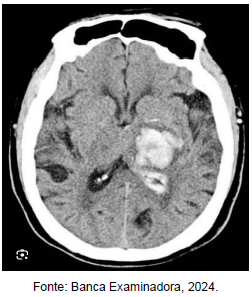

Paciente, 67 anos, hipertenso prévio, dá entrada no pronto atendimento com quadro súbito de hemiparesia esquerda, com a tomografia ilustrada na figura acima, e PA de 180x120 mmHg. Diante do quadro é correto afirmar que: